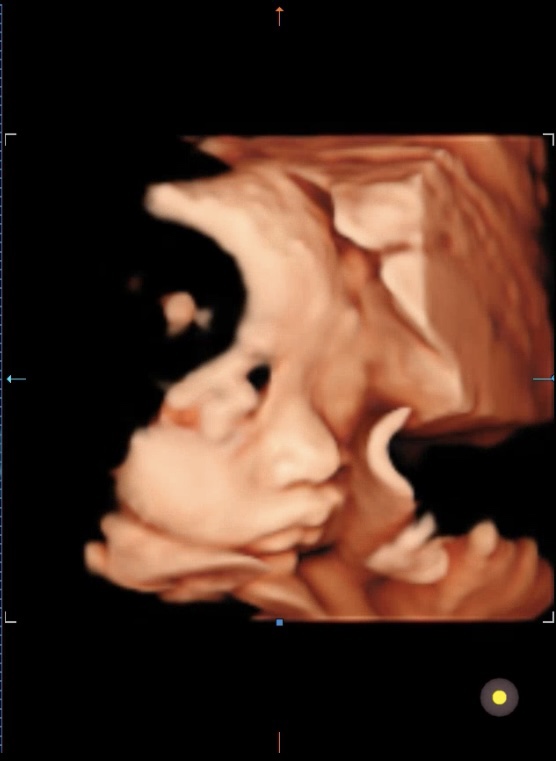

둘째임신) 34주 4일 임신후기

이틀전에 다녀온 병원 34주다 이제 두세번만 병원 더 가면 출산 ㅎㄷㄷㄷㄷㄷㄷ ???? 출산 무...